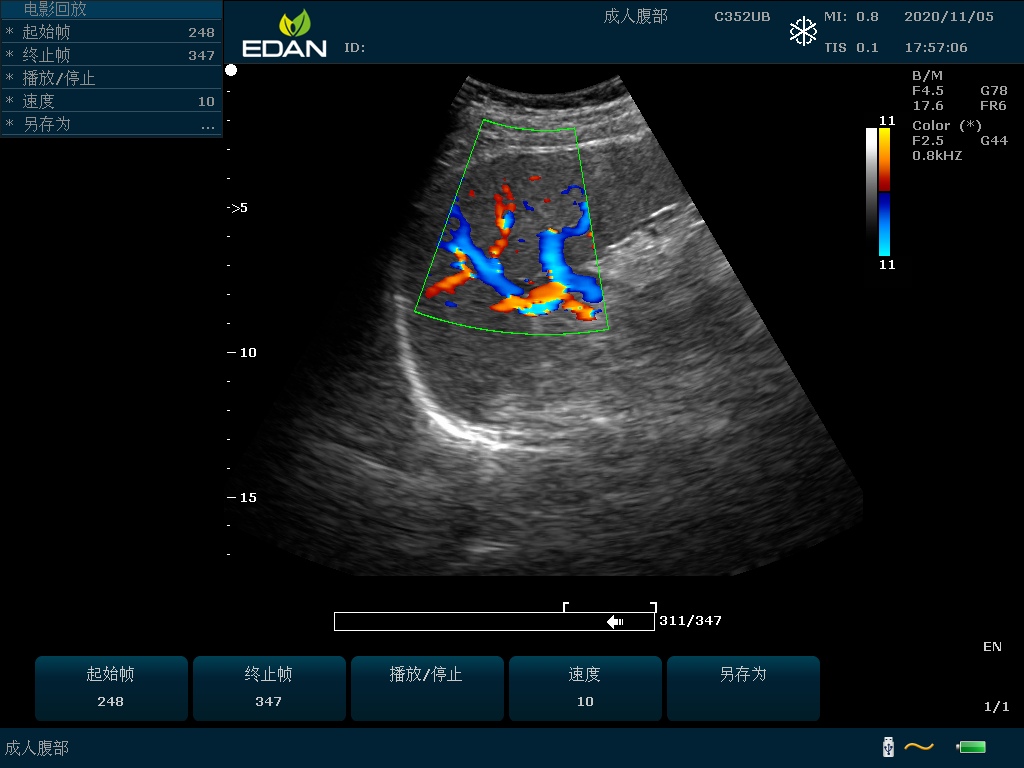

Особенность U60 Edan — расширенное применение. Ультразвуковой аппарат рекомендован для абдоминальных исследований, гинекологии и акушерства, кардиологии, педиатрии, урологии, изучения малых органов, сосудов. Для U60 Edan используются конвексные, линейные, фазированные и внутриполостные датчики.

Передовые технологии позволяют повысить качество визуализации в несколько раз. УЗИ-аппарат U60 Edan отличается возможностью быстрой настройки визуализации. Специальные функции позволяют моментально отображать данные за счет быстрой оптимизации параметров. Режимы визуализации: B-mode, M-mode, Color Doppler, Power Doppler Imaging, Pulsed Wave Doppler, Continuous Doppler.